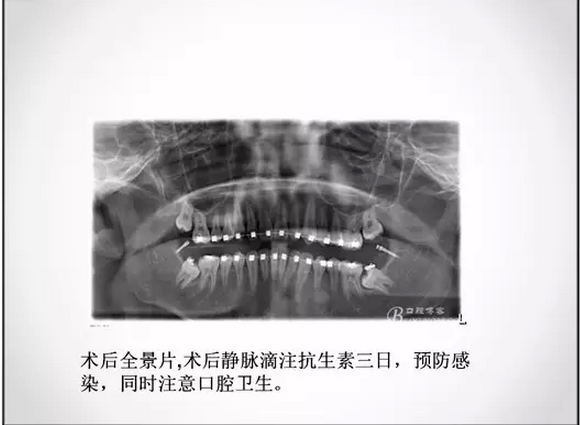

埋伏牙正畸治療中的外科開窗術(shù)

3.jpg